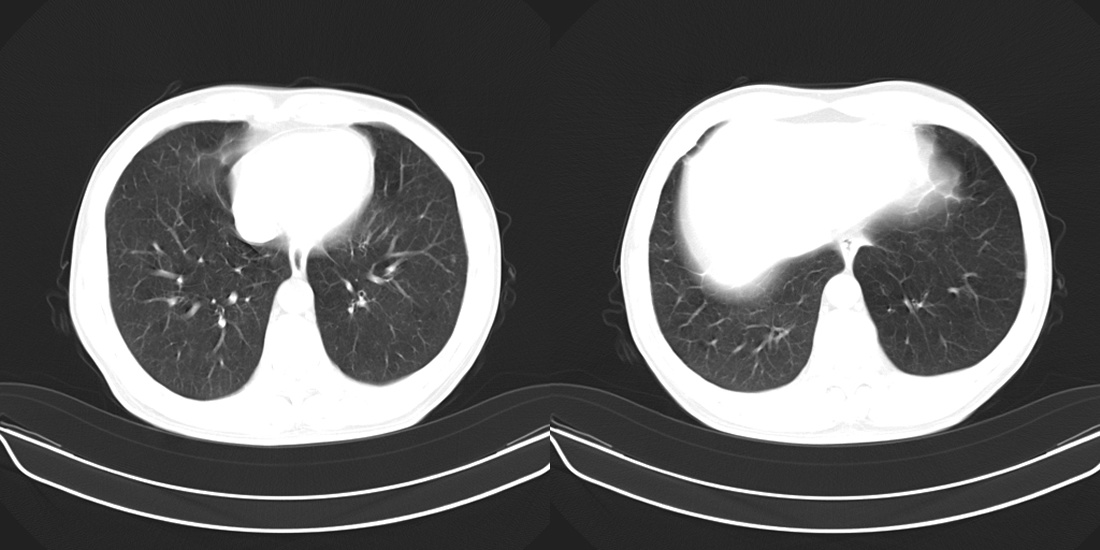

标题: CT10251:男性56岁,结核球? [打印本页]

标题: CT10251:男性56岁,结核球?

56岁男性,低热、消瘦,曾x线诊断肺结核。

两肺结核,左肺结核球。

双肺结核伴左上肺结核球形成

两肺多形性病变,支持肺结核.

两肺多形性病变,且在结核好发部位。支持肺结核.